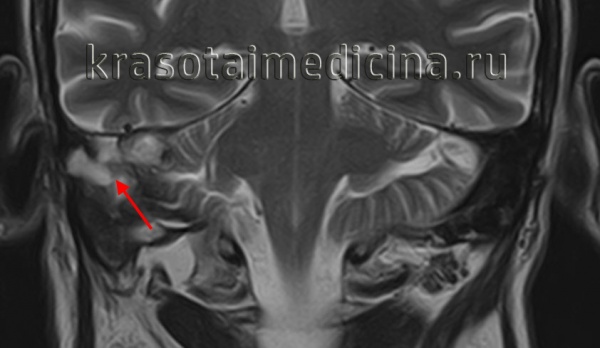

(Слева) При аксиальной МРТ Т1 ВИ у этого же пациента визуализируется экспансивная гиперинтенсивная ХГ-ВП. Жидкость в сосцевидном отростке имеет промежуточный сигнал, преимущественно за счет содержания белка.

(Справа) При аксиальной МРТ Т2 ВИ у этого же пациента визуализируется гиперинтенсивное экспансивное образование ВП, в котором находятся мелкие гипоинтенсивные очаги (отложения гемосидерина). Классическая холестериновая гранулема имеет гиперинтенсивный сигнал на Т1 и Т2. «Запертая» жидкость в сосцевидном отростке также гиперинтенсивна.